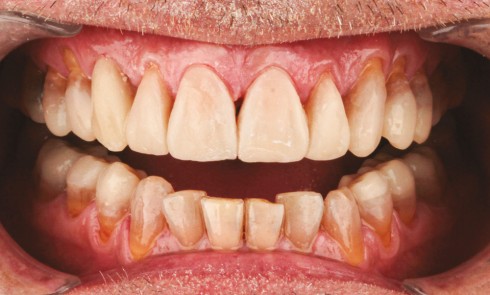

Article réservé à nos abonnés Les vrais critères de choix de la Dimension Verticale d’Occlusion thérapeutique : applications cliniques

À travers trois situations cliniques différentes, illustrées par une anamnèse, des examens cliniques et radiologiques, une réflexion est engagée pour...